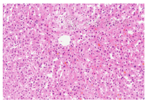

5例患者中有3例于我院进行了肝活组织病理学检查,患者编号分别为1、2和4。其中第1例患者肝穿刺活组织学检查为疾病的第1次发作,第2例患者为疾病的第2次发作,第4例患者为疾病的第9次发作。3例患者的病理学均提示肝脏小叶结构清晰,肝小叶内未见坏死灶;汇管区无明显扩大和明显炎症。仅仅表现为小叶中心毛细胆管淤胆(图1,图2,图3,图4)。其余2例患者就诊于我院时,已有多次典型的发作性黄疸,发作间期无任何症状,在治疗随访的过程中胆红素逐渐恢复正常,因此未行肝活组织病理学检查。

常见的导致直接胆红素升高的遗传性疾病包括:Dubin-Johnson综合征、Roter综合征、BRIC。Dubin-Johnson综合征的病理特点为:肝小叶中央静脉周围肝细胞内有大量脂褐素-黑色素复合物沉积;Roter综合征病理上无明显的改变,表现为正常的肝脏组织。BRIC病理学特征为:发作时小叶中心胆汁淤积,在扩张的毛细胆管、肝细胞、或Kupffer细胞内可见胆汁淤积。较少见的病变包括小叶中心局灶性单核细胞浸润伴或不伴有肝细胞变性、坏死;偶有细胆管增生。随着发作缓解,肝脏病理改变逐步恢复正常。我科5例患者中有3例于我院进行了肝活组织病理学检查,其中1例患者虽然经历了9次发作,但其肝组织仅仅表现为小叶中心毛细胆管淤胆,没有肝小叶及汇管区的慢性损伤表现。符合BRIC的病理表现。